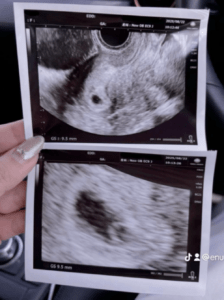

赤ちゃんが浮いた瞬間(@kokogun5656さんより提供)

投稿されていたエコー動画が撮影されたのは、妊婦健診で初めて腹部エコーを行ったときでした。

当時、まだ赤ちゃんは数cmほどの大きさ。それでも画面に映る姿を見て、ママさんは「可愛い」と看護師さんと一緒に笑っていたといいます。

エコー写真(@kokogun5656さんより提供)